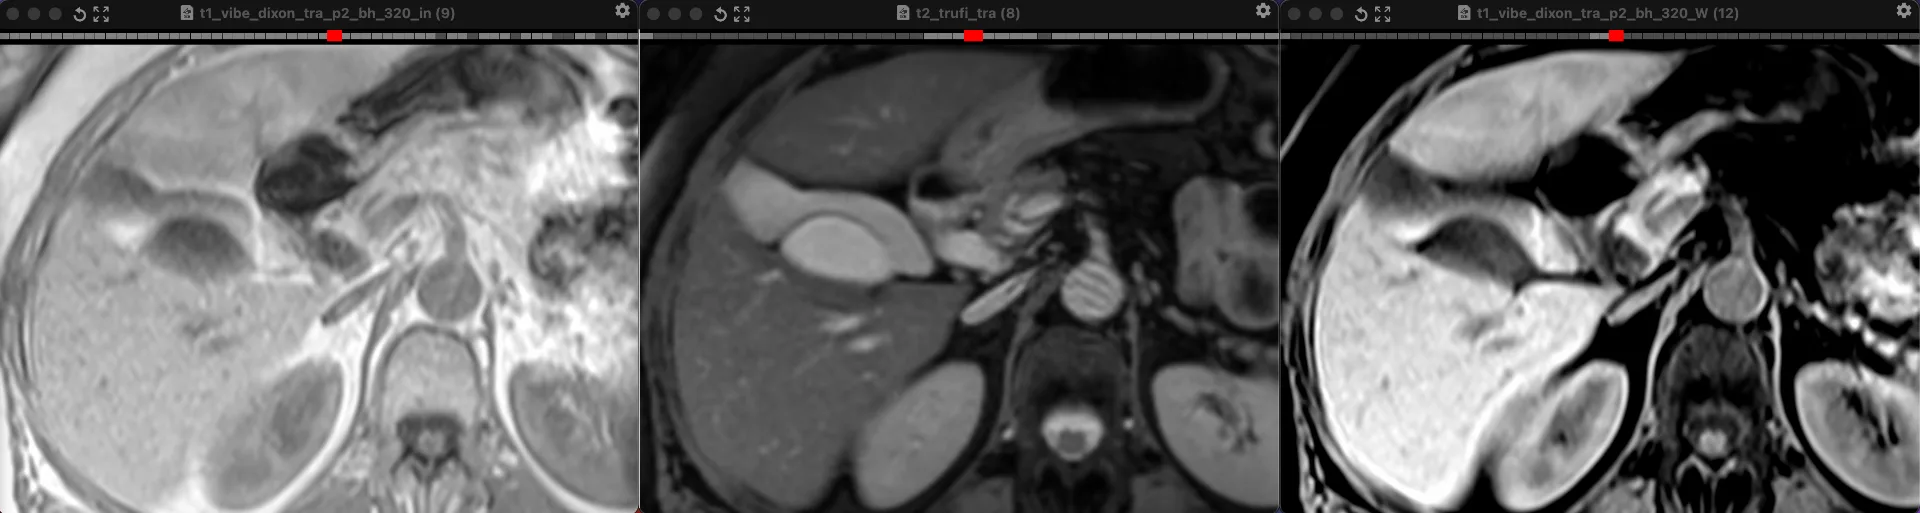

ЖЕНЩИНА 38 лет, фокальное изменение печени выявлено на УЗИ.

Повторные #КТ (с разницей в 2,5 месяца) без динамики. Имеется медленное, постепенное, слабоинтенсивное накопление контраста от периферии к центру.

На #МРТ - очень высокий сигнал на Т2, низкий на Т1, «лучистые» контуры. Истинное ограничение диффузии (ADC=460±109х10-6 кв.мм/с). Накопление контраста такое же, но на МРТ лучше видны краевое узелков накопление в артериальную фазу, тотального контрастирования нет даже на отсроченной фазе (через 5 минут).

Картина характерна: это гиалинизированная/ #склерозированнаягемангиома. Характерное стяжение контура является свидетельством склерозирования: уменьшения объёма, «рубцевания».

Гемангиомы с суженными кавернозными пространствами из-за склероза имеют большее количество более толстых и неровных перегородок, которые могут препятствовать диффузии молекул, что приводит к снижению значений ADC.

Склерозированные гемангиомы печени — это редкие доброкачественные поражения, которые часто трудно отличить от злокачественных, ибо они не имеют типичных для кавернозных гемангиом признаков.

Но! Часть признаков все равно сохраняются:

1. Значительный гиперсигнал на т2

2. Резкие, хоть и неровные, контуры

3. Центрипетальное, и иногда с приставочными узелками накопления контраста на артериальной фазе, контрастирование, пусть и неполное.

4. Стабильность в динамике